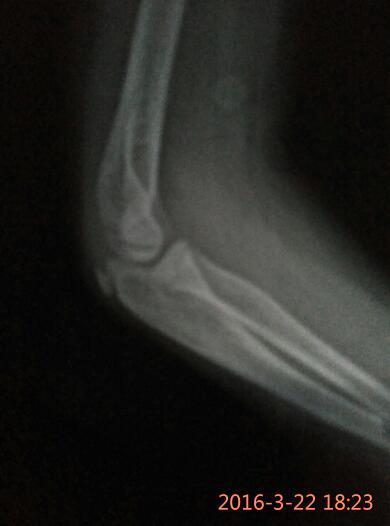

孩子胳膊摔伤,拍的片子,麻烦帮忙看看是骨头掉一块渣吗? 点击展开 两只猴子的妈妈 2016-03-22 18:29 满意回答 小孩子多大,鹰嘴那个位置痛吗,看起来不太像,要看症状才好说 cn#BfBVkBQufu 2016-03-22 18:31 宝宝知道提示您:回答为网友贡献,仅供参考。 相关问题 我脚是2个月前摔伤的,当时拍了片子,医生说骨头 宝宝胳膊摔伤拍过片子可以打预防针吗 我家孩子胳膊摔伤做过手术可现在己恢复3个月才只能弯曲70度怎么办拍过片子都正常